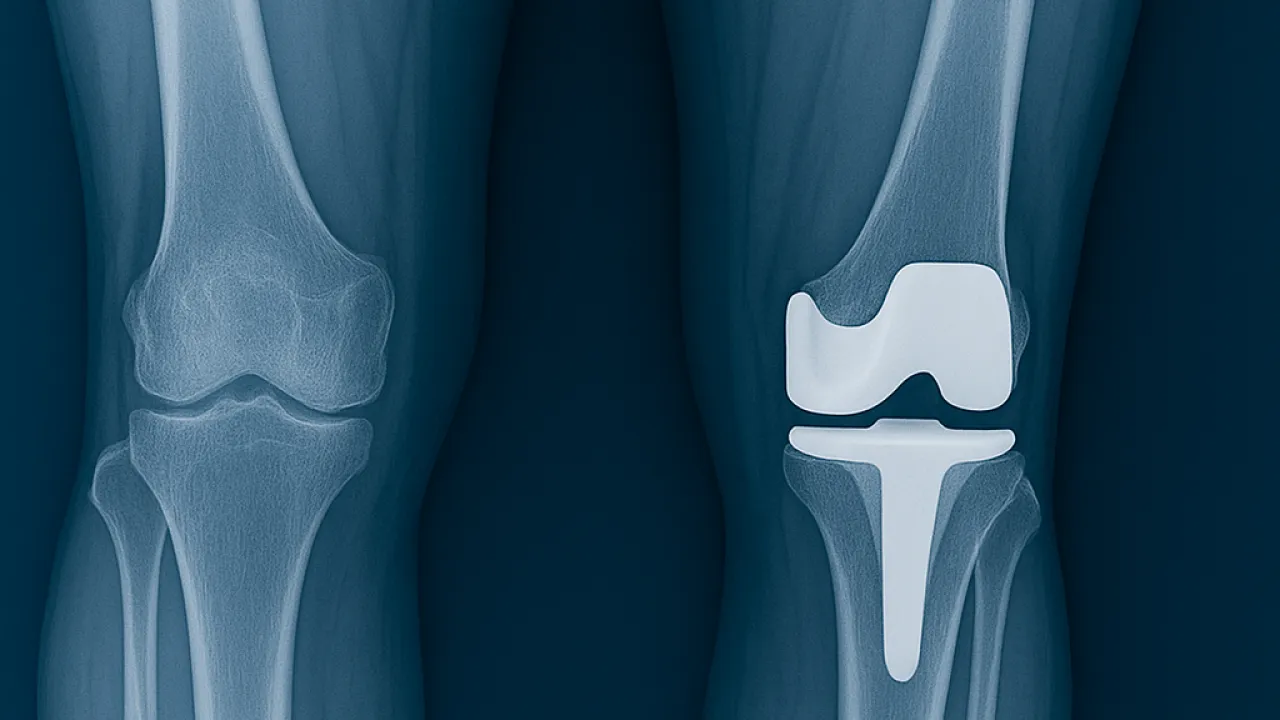

Diz kireçlenmesi (diz osteoartriti), eklem kıkırdağının aşınması sonucu ağrı, hareket kısıtlılığı ve yaşam kalitesinde ciddi düşüşe yol açar. İleri evrelerde en kalıcı çözüm diz protezi ameliyatıdır. Günümüzde protez cerrahisinde klasik yöntemlere ek olarak robotik diz cerrahisi de uygulanmaya başlanmıştır. Bu yöntem uzun yıllardır yurt dışında kullanılmaktadır. İzmir'de robotik diz cerrahisi yapan hekimlerden birisiyim. Deneyimim ise 2015 Yılında Fransa'nın LYON şehrinde Croix Rousse Hastanesi'nde çalıştığım sürede başladı. Burada gözlemci olarak değil, doktor olarak çalıştım. Bu sayede robotik diz cerrahisiyle tanışma fırsatım oldu. Her yöntem gibi artıları ve eksileri olan bu yöntemde de hasta seçimi ve uygun tedavi en önemli belirleyici unsurlardır.

Klasik yöntemde cerrah, röntgen ve MR görüntülerini değerlendirerek ameliyat öncesi planlama yapar. Ameliyat sırasında ise bu plana dayanarak kemik kesilerini manuel olarak gerçekleştirir.

Robotik cerrahi, ameliyat öncesinde 3 boyutlu görüntüleme teknolojileri kullanarak hastanın dizini sanal ortamda modellenmesini sağlar. Bu sayede protez yerleştirilmeden önce tüm ölçümler detaylı şekilde yapılır.

Ameliyat sırasında robotik sistem, cerrahın elini yönlendirir ve kemik kesilerini yüksek hassasiyetle gerçekleştirir.